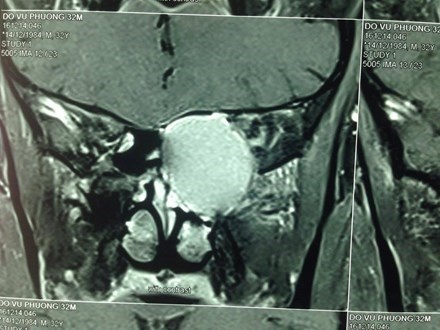

Bé gái người Trung Quốc (3 tuổi) mắc chứng bệnh "não úng thủy" khiến đầu to gấp 4 lần người bình thường và có thể nổ bất cứ lúc nào.